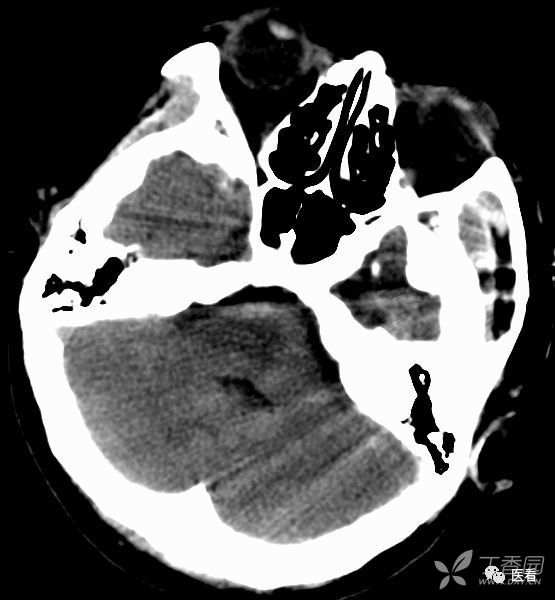

亨氏暗区

颅底(致密)骨产生的横行或放射状伪影,与设备性能也有关系

下图为16拍MSCT,伪影较轻。

此图为双排螺旋 CT图像, 伪影较16层及以上MSCT显著的多。